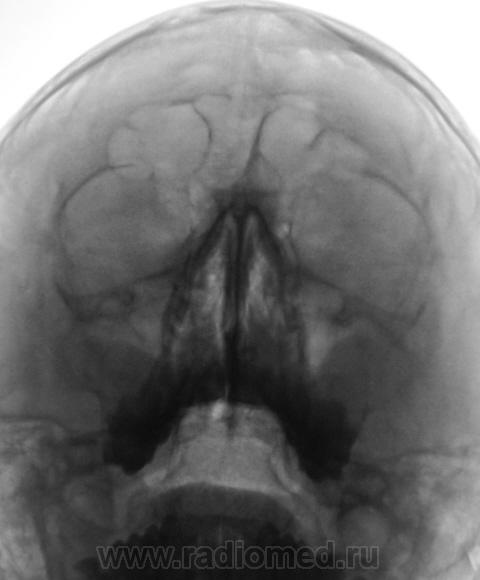

Пациент направлен оториноларингологом на рентгенографию придаточных полостей носа.

Произведено стандартное исследование.

В центральной ячейке лобной пазухи - уровень жидкости - фронтит. в верхнечелюстных пазухах - картна кист, и сфеноидит...

Ячейки решетчатых костей с обеих сторон затемнены, имеются пристеночные теневые наслоения в обеих в/челюстных пазухах, больше у наружных стенок, , с четкими выпуклыми контурами, носовые ходы сужены. R-картина синуита. В наличии горизонтальных уровней в лобных пазухах сомневаюсь. А что бы определиться с основной пазухой, хорошо бы сделать боковую проекцию.

То же склонен видеть уровень жидкости в лобных (видно что повторяет наклон), пристеночное подушкообразное утолщение слизистой в верхнечелюстных, сфеноидит.

Согласна с коллегой по поводу сомнительности затемнения лобных пазух, это может быть обусловлено ячейками решетчатой кости.